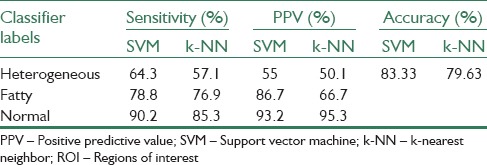

The second experiment is performed to show the effectiveness of the hierarchical classification scheme. This experiment contains a test over automatically selected ROIs, as in the first experiment, and a comparison with the results of Minhas et al.[7] At the first step of the classification, the diffused and focal classes are denoted as classes 1 and 2, respectively. At the second step, repeatedly, the fatty class is marked as Class 1 and the normal one as Class 2. The selected ROIs are examined by SVM and k-NN classifiers by the use of LOOCV method. Table 1 illustrates the Se and PPV of each class in each step and the Acc of each step.

Table 1.

Results of the one-against-all nonhierarchical scheme over 25 overlapped ROIs (automatic selection) by the use of leave one out cross validation

Tables 3 and 4 illustrate the Se and PPV of each class and the overall Acc using LOOCV method.

Table 3.

Results of leave one out cross validation and hierarchical classification scheme for the third test (considering 25 overlapped blocks) in comparison with method of Minhas et al.[7]

According to Table 3, the Se of 100% and 90.3% to detect the heterogeneous and fatty cases, respectively, shows the efficiency of the segmentation method. Furthermore, the PPVs of more than 90% represent efficient precision of the proposed scheme. Moreover, the results of this Table 3 illustrate the efficiency of SVM classifier compare to k-NN.

With the comparison between Tables 3 and 4, this experiment also illustrates that, using the automatically selected ROIs leads to better performance compared to the manually selected ROI. Moreover, in manually selected case, the results depend on the expert's assessment.

According to the results in Table 1, by considering 25 ROIs, this method is reliable and can be used in CAD systems in practical diagnosis of fatty and heterogeneous livers based on US images. As this Table 1 shows, the proposed method gives the Se of 100% for detecting both heterogeneous and fatty livers at the first and the second steps using SVM classifier. This shows the complete detection and quite correct diagnosis of these diseases, of course, for the available dataset.

Furthermore, we have achieved the overall Acc of 97.9% that is higher compared to the approach of Minhas et al.[7] with overall Acc of 95.4% in the same condition. In addition, the method of selecting ROIs in the proposed scheme is completely automatic with lower computational cost than the method of Minhas et al.[7] In the scheme of Minhas et al.,[7] a medical expert had manually extracted ROIs from training US images. A given US image was first cropped to extract a wide region near the central lobe. The continuous wavelet transform (CWT) of the cropped image was then taken with nine different scale parameter values. Thus, a single pixel of the original image could be represented as a nine-dimensional feature vector. As each of the manually selected ROI was 64 × 64-pixels, therefore, the total number of pixels available for training became 4,096 for a single ROI. Thus, the total number of examples for training the one class SVM for all the 88 images was 360,448. For efficient training of the one class SVM, the number of examples was reduced from 360,448 to 4,096 using k-means clustering. The cluster centers were then used to train the one-class SVM. For segmentation, the CWT of a given US image was taken, and the nine-dimensional representation of each pixel was subjected to the one-class SVM and some parameters were computed. After normalizing, applying morphological operations, filtering and finding the maximum value of pixels in each resulting image, the center of the proper ROI was found. Therefore, the method of ROI selection in Minhas et al.[7] is semi-automatic with high computational complexity. Moreover, their classification method is not a hierarchical one.